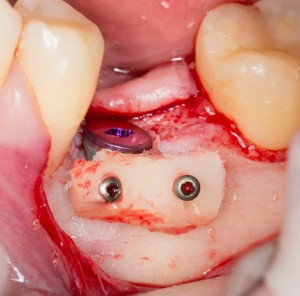

И тут пациентка сказала: «Постойте! У меня так легко проходят операции, так почему бы нам не поставить большее количество имплантов в правой части? В идеале, чтобы каждая коронка опиралась на свой имплантат — я больше не хочу мостовидные протезы!» Желание пациента — закон. Поэтому на правой стороне мы усложняем работу:

третий этап работы: слева уже установлены временные протезы на имплантах, а справа удалены четыре зуба и одновременно установлены четыре импланта

Как вы думаете, сколько времени заняла третья хирургическая операция? 60 минут! Легко, быстро и комфортно. А главное — результативно!